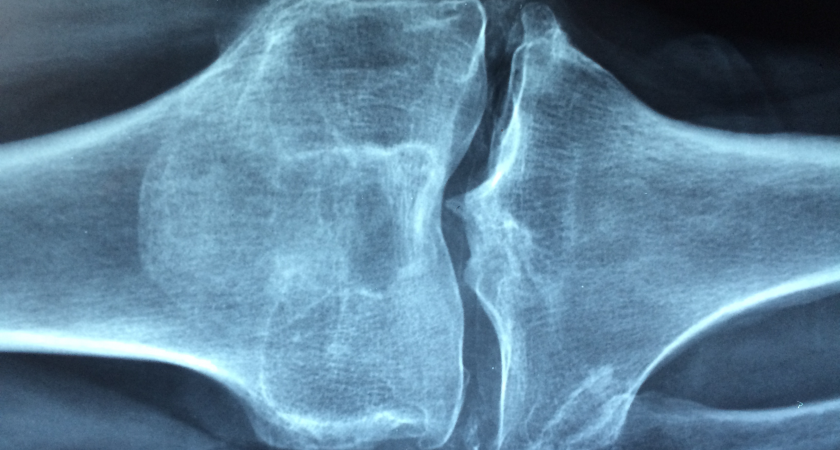

Дисплазия соединительных тканей - это генетическая особенность, при которой волокна соединительной ткани обладают повышенной способностью к растяжению, иногда выходящей за рамки физиологических потребностей того или иного участка тела. Поскольку соединительная ткань присутствует повсеместно, этот синдром носит системный характер, но в ортопедическом ключе мы прежде всего рассматриваем его влияние на связки, сухожилия и мышцы. То есть вот эта тройка имеет возможность перерастянуться лишний раз больше, чем требует тот или иной участок тела.

С одной стороны, она дает суставам необычную подвижность, делает их «живыми». С другой — меняет естественные векторы движения, и с раннего возраста это создает неправильные точки приложения сил. ДСТ напрямую влияет на будущую износостойкость суставов и чревато различными последствиями. Например, со стороны стопы это часто ведет к плоскостопию и его осложнениям. Для коленных суставов проблема может быть в основном эстетической — избыточном выпячивании коленей назад. В тазобедренных суставах у взрослых изменения обычно малозначимы, но в младенчестве, до начала ходьбы, повышенная растяжимость может привести к вывиху. Со стороны спины ДСТ нередко приводит к формированию сколиоза различной степени. В плечевых суставах гипермобильность проявляется склонностью к подвывихам, хроническим щелчкам и болевым синдромам. Локтевые и лучезапястные суставы, а также пальцы кистей чаще демонстрируют лишь эстетический эффект избыточного сгибания-разгибания и легкую нестабильность.